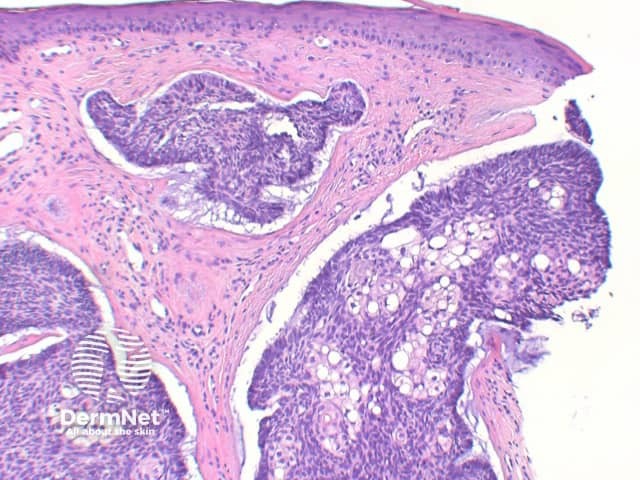

The key feature of basal cell carcinoma at low power magnification is of a basaloid epithelial tumour arising from the epidermis (figure 1). The basaloid epithelium typically forms a palisade with a cleft forming from the adjacent tumour stroma (figure 2). Centrally the nuclei become crowded with scattered mitotic figures and necrotic bodies evident (figure 3). A useful distinguishing feature from other basaloid cutaneous tumours is the presence of a mucinous stroma (figure 4). Some tumours may also show foci of regression, seen as areas of eosinophilic stroma with lack of basaloid nests.

Figure 4

Infundibulocystic BCC: This variant shows multiple small cysts containing cornified material with differentiation towards the infundibulum. In distinguishing from trichoepitholioma, it lacks papillary mesenchymal bodies, but frequently retains a mucinous stroma.

Sebaceous differentiation: Basal cell carcinoma can also occasionally show areas of significant sebaceous differentiation (figure 12). This needs to be differentiated from sebaceoma, as discussed below.